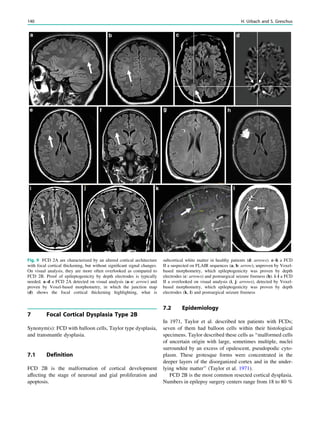

Magnetic Resonance Spectroscopy inChronic Epilepsy Friedrich G. Woermann Contents 1 Methodological Considerations.......................................... 57 2 MRS: Diagnostic Accuracy in Epilepsy............................ 59 3 MRS in Temporal Lobe Epilepsy and Hippocampal Sclerosis................................................................................. 60 4 MRS in Extratemporal Neocortical Epilepsy .................. 60 5 MRS in Neocortical Epilepsies Due to Malformations of Cortical Development..................................................... 60 6 MRS in Tumors ................................................................... 61 7 MRS in Metabolic Disease and Epilepsy.......................... 61 8 MRS in Juvenile Myoclonic Epilepsy ............................... 61 9 Conclusion ............................................................................ 62 References...................................................................................... 62 Abstract The cornerstone of lesion detection in chronic epilepsy is structural imaging, mainly magnetic resonance imaging. Metabolic information from magnetic resonance spec- troscopy (MRS) might serve as an additional or as a surrogate marker for the epileptogenic lesion. MRS might also help to differentiate similarly appearing lesions from one another; it might detect contralateral/ remote dysfunction. However, the clinical role of MRS is unclear, albeit another non-invasive diagnostic tool. Magnetic resonance spectroscopy (MRS) measures the concentrations of metabolites in the brain noninvasively. In epilepsy, MRS aims to aid the identification of the epilep- togenic lesion. Ultimately it aims to predict the postopera- tive outcome after surgical removal of these lesions. MRS results in epilepsy show similar abnormalities (loss of neuronal markers) associated with different pathological entities in different anatomical locations (Table 1). It is believed that MRS might give insights into the mechanisms of seizure generation (McLean et al. 2008). 1 Methodological Considerations Physical principles underlying MRS are the same as for MRI, which means that most clinical scanners can be used for MRS. In epilepsy, proton-MRS studies are most com- mon. The 1 H nucleus (a single proton) is abundant. MRS exploits minor differences in resonance frequency of 1 H depending on the metabolite to which protons are bound. MRS of certain brain metabolites needs techniques to exclude the strong signals arising from water and macro- molecules (lipids and proteins, which both contain large numbers of protons) in order to study the smaller signals from more interesting metabolites (amino acids, sugars, etc.). Techniques to suppress the water peak and to reduce F. G. Woermann (&) MRI Unit, Mara Hospital, Bethel Epilepsy Center, 33617 Bielefeld, Germany e-mail: friedrich.woermann@mara.de H. Urbach (ed.), MRI in Epilepsy, Medical Radiology. Diagnostic Imaging, DOI: 10.1007/174_2012_761, Ó Springer-Verlag Berlin Heidelberg 2013 57

• 62.

or spatially excludeunwanted macromolecule signals are inherent parts of the examination. Spatial exclusion (also known as outer volume suppression) is needed because of intense lipid signals arising from the scalp. Disturbances from fat, but also inhomogeneities near the base of the skull, can make MRS a tedious technique in epilepsy as epilep- togenic lesions are often mesiotemporal or cortical. In vivo MRS measures only metabolites present at con- centrations of about 1 mM or higher. The metabolites studied are shown in Fig. 1. At long echo times (TE C 135 ms), a large signal is present from N-acetyl aspartate (NAA), a neuronal marker, or better, a marker of neuronal function. Other peaks stem from creatine plus phosphocreatine (Cr) supposedly representing the energy level and cellular den- sity; choline-containing compounds (Cho) represent mem- brane turnover. At shorter echo times (e.g., 30 ms, as shown in Fig. 1), additional interesting peaks can be detected from myo-inositol (Ins; representing gliosis) and glutamate and glutamine (Glx; excitatory amino acids), but sophisticated modeling is necessary to distinguish the latter from the overlapping peaks, and baseline irregularities remain a major source of error at shorter echo times. In single-voxel spectroscopy (SV-MRS), slice-selective excitation in three orthogonal planes excites a cuboid volume at their intersection (Fig. 1). The other common localization tool uses phase encoding, as in imaging. This is known as spectroscopic imaging (MRSI), sometimes called chemical shift imaging (CSI), and produces a slice with a grid of multiple voxels (Fig. 2). Since the areas under the curves of metabolite signals are directly proportional to their concentrations in the tissue, spectra can be looked at qualitatively, or metabolite con- centrations can be estimated quantitatively. Most com- monly, the ratio of one peak to another is reported, such as NAA/Cr or NAA/(Cr ? Cho). This has the advantage that any temporal, spatial, or intersubject differences in machine performance cancel out. Ratios can vary both in different tissues of the brain and in disease. Table1 Textbook knowledge* on MRS in surgically remediable lesions in chronic epilepsy: low NAA and moderatly increased Cho are frequent findings. Pathology MRS finding* Hippocampal sclerosis/mesial temporal sclerosis (MTS) ; NAA in hippocampus, temporal lobe; NAA/Cho 0.8 suggests MTS; if scan patient within 24 hours of seizure, lactate/lipid peaks reported Benign tumours : Cho, ; NAA (vs. malignant tumours: :–::: Cho, : lactate/lipid) Ganglioglioma : Cho, ; NAA Diffuse astrocytoma, low grade :–:: Cho, ; NAA typical but not specific; relatively high Ins/Cr (compared to anaplastic astrocytoma) DNT Nonspecific (: Cho, ; NAA), but lactate present in some Focal cortical dysplasia ; NAA, (: Cho); but ; NAA less pronounced compared to low grade astrocytomas Other malformations of cortical development Heterotopia: NAA and Cho are variable; Pachygyria-Polymicrogyria: ; NAA Tuberous sclerosis ; NAA/Cr, : Ins/Cr; lactate in seizure onset? Cavernoma (-) Porencephaly Absence of normal brain metabolites Scars due to chronic cerebral infarction ; NAA Posttraumatic scars ; NAA Rasmussen encephalitis ; NAA, ; Cho; : Ins, : glutamine/glutamate Hemiconvulsion-Hemiplegia-Epilepsy-Syndrome (following a febrile status epilepticus) Within 24 hours of status: lactate and lipids; later: ; NAA Arteriovenous Malformation (-) Hemimegalencephaly (a hemispheric malformation of cortical development) Progressive ; NAA, : Cho, : Cr, : Ins Sturge Weber Syndrome ; NAA, : Cho Neurocysticercosis ; NAA, ; Cr; : Cho, : lactate, : alanine *extracted and modified from: Osborn A (Ed). Diagnostic Imaging—Brain. Amirsys, Salt Lake City, 2004 NAA N-Acetyl-aspartate; Cho choline, Cr creatine, Ins myo-inositol, ; decrease, : increase, (-) no information available 58 F. G. Woermann

• 63.

2 MRS: DiagnosticAccuracy in Epilepsy In the evaluation of patients with epilepsy, the potential value of 1 H-MRS (or -MRSI) depends on the method’s ability to detect localized metabolic changes not only in clear-cut cases with visible lesions, but also in patients with normal MRI (‘‘MRI-negative’’). Ultimately, the clinical value of 1 H-MRS in this patient group is based on studies correlating presurgical measurements with postsurgical seizure and neuropsychological outcome. Recently, diagnostic accuracies of different neuroimag- ing techniques in epilepsy were thoroughly reviewed (Whiting et al. 2006; Burch et al. 2012). MRS studies in epilepsy were included in case they allowed the computa- tion of test-quality data correlating MRS results and post- surgical outcome or other gold standards in individual patients (Cross et al. 1996; Cendes et al. 1997; Knowlton et al. 1997; Achten et al. 1998; Kuzniecky et al. 1998; Li et al. 2000; Antel et al. 2002; Lee et al. 2005). These reviews resulted in very careful statements (‘‘There was a trend for localisation of abnormalities to be associated with Fig. 1 Single-voxel short-TE MRS in a patient with right-sided hippocampal sclerosis. NAA on the affected side (a) is lower than on the contralateral side (c). The size of the voxel is tailored to atrophy of right-sided hippocampus to reduce the diluting influence of nearby CSF (b). Modified from Woermann et al. (1999b) Fig. 2 Epilepsy patient with large heterotopia in a pericentral region on the right side. MR spectroscopic imaging produced a slice of multiple voxels (a). NAA can be quantified and concentration can be displayed as a color map (b). This map illustrates that NAA concentration varies within the large malformation of cortical development. Modified from Woermann et al. (2001) Magnetic Resonance Spectroscopy in Chronic Epilepsy 59